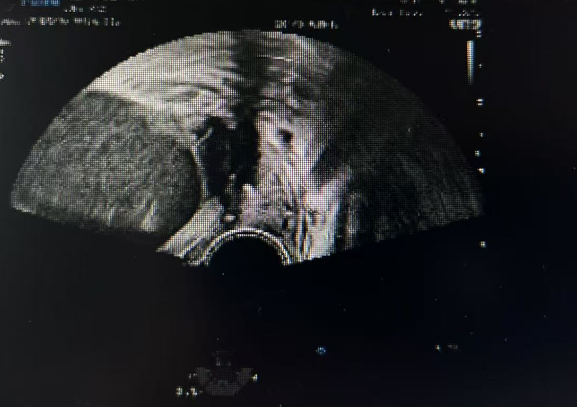

这位历经艰辛才迎来首次妊娠的高龄孕妇,在孕22+5周时遭遇「宫颈机能不全」危机——超声显示宫颈闭合段仅剩0.2cm(正常应>2.5cm),宫颈内口呈"漏斗状"扩张,羊膜囊随时可能脱出。

当天下午,我院产科团队为其实施紧急「宫颈环扎术」,通过特制缝合线在宫颈内口处编织出"生命堤坝"。

术前术后彩超对比图

手术仅耗时17分钟,出血量10ml,术后恢复良好,目前孕26周的毛女士已回归正常产检。